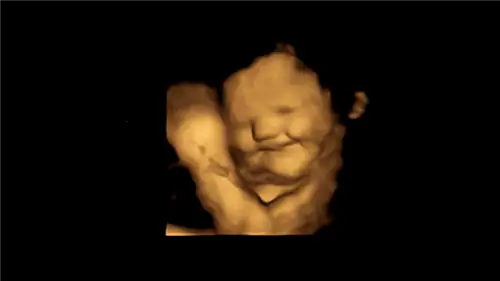

Под воздействием зелени плод резко хмурится.

В исследовании, опубликованном на этой неделе в журнале Psychological Science, было проведено 4D-ультразвуковое сканирование 100 беременных женщин в возрасте от 18 до 40 лет на 32-й и 36-й неделях беременности, чтобы увидеть, как плод реагировал на воздействие вкусов пищевых продуктов. съедены их матерями. Мам попросили не употреблять пищу или ароматизированные напитки за час до сканирования, а также не есть и не пить морковь или капусту в день сканирования в качестве контроля. Затем матерям давали одну капсулу, содержащую около 400 мг порошка моркови или 400 мг капусты, примерно за 20 минут до каждого УЗИ..

При контакте с морковью плод показал «смеющееся лицо». Капуста, с другой стороны, часто приводила к реакции «плачущего лица».